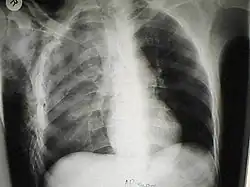

Significant cases of subcutaneous emphysema are easy to diagnose because of the characteristic signs of the condition.[1] In some cases, the signs are subtle, making diagnosis more difficult.[13] Medical imaging is used to diagnose the condition or confirm a diagnosis made using clinical signs. On a chest radiograph, subcutaneous emphysema may be seen as radiolucent striations in the pattern expected from the pectoralis major muscle group. Air in the subcutaneous tissues may interfere with radiography of the chest, potentially obscuring serious conditions such as pneumothorax.[18] It can also reduce the effectiveness of chest ultrasound.[28] On the other hand, since subcutaneous emphysema may become apparent in chest X-rays before a pneumothorax does, its presence may be used to infer that of the latter injury.[13] Subcutaneous emphysema can also be seen in CT scans, with the air pockets appearing as dark areas. CT scanning is so sensitive that it commonly makes it possible to find the exact spot from which air is entering the soft tissues.[13] In 1944, M.T. Macklin and C.C. Macklin published further insights into the pathophysiology of spontaneous Macklin's Syndrome occurring as a result of a severe asthmatic attack.